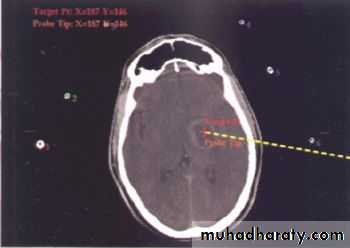

• Indications for Aspiration (Burr hole ± Stereotaxis):

• Multiple abscesses.

• A deeply seated abscess.

• A critical location (e.g. motor or speech area).

• Poor general condition of the patient.

Stereotactic Aspiration of Brain Abscess